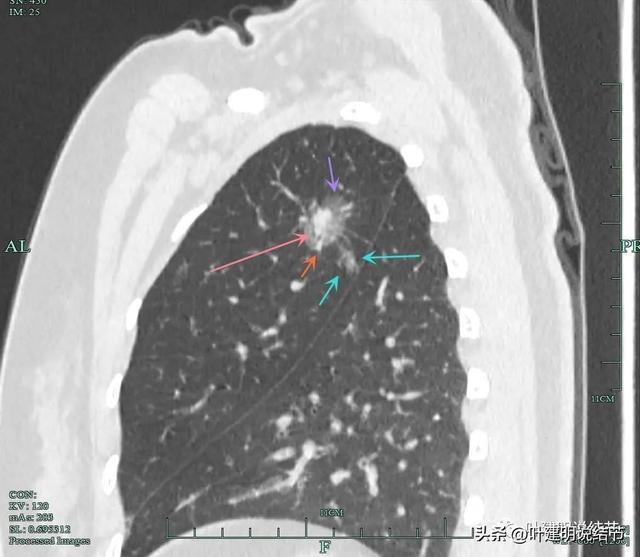

摘要:,,近日有報道稱,一位患者通過食用三七成功消除肺部結(jié)節(jié),這一自然療法展現(xiàn)出奇跡般的效果。這一療法為肺結(jié)節(jié)患者提供了新的選擇,展示了食療在疾病治療中的巨大潛力。患者應(yīng)注意,每個人的身體狀況和結(jié)節(jié)情況不同,此方法不...